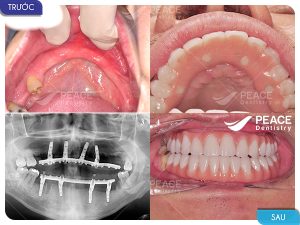

Hình ảnh tẩy trắng răng